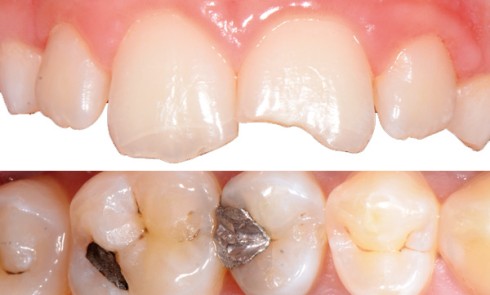

Article réservé à nos abonnés Économie tissulaire et préparations partielles

« No-Post, No-Crown » Formes de préparation contemporaines pour les restaurations adhésivesI. Secteur antérieurII. Secteur postérieurSolène Marniquet, Gil Tirlet L’overlay le successeur...

Article réservé à nos abonnés No-Post, No-Crown. Formes de préparation contemporaines pour les restaurations adhésives

Depuis deux décennies, le concept d’adhésion a considérablement bouleversé la pratique de l’art dentaire et le mode de pensée du...